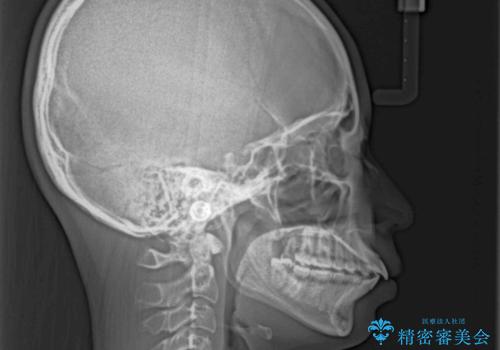

- 上下の前歯が突出しており、口が閉じにくいとのことで来院された患者様です。

上下前歯が著しく前突している状態であったので、上下左右の第1小臼歯4本を抜歯し、ワイヤー装置にて矯正治療を行うこととしました。

舌の突出癖により、前突になったと考えられたため、舌のトレーニングをしっかりと行うよう指導しました。